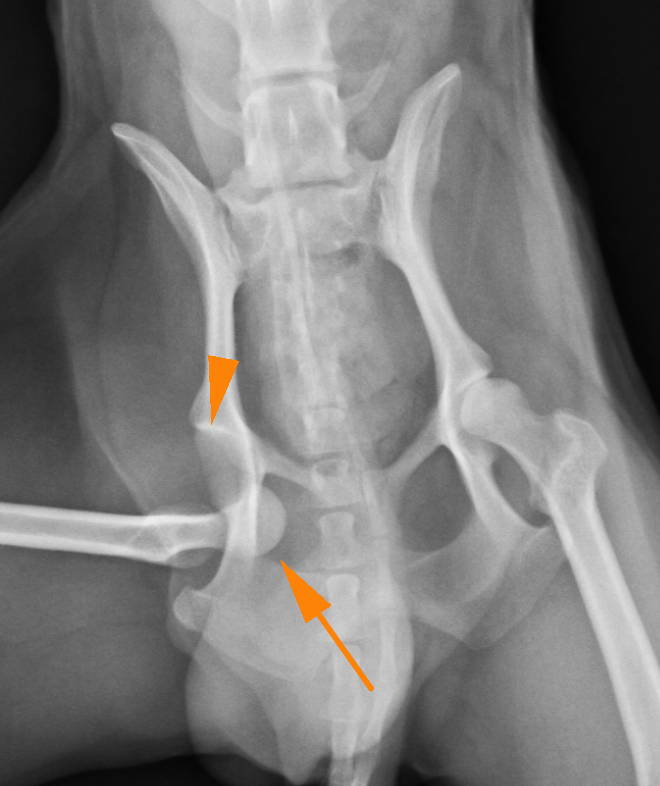

股関節とは骨盤の寛骨臼と呼ばれる凹みの部分に、大腿骨の大腿骨頭と呼ばれる球状の骨がはまることで関節しています。それが外傷や、寛骨臼の形成不全などによって抜けてしまうことを股関節脱臼といいます。

股関節が脱臼すると強い疼痛を引き起こし、足を地面に着けることができなくなり挙上してしまいます。股関節脱臼は脱臼する向きによって大きく2つに分けられます。90%が頭背側脱臼というもので、前方かつ、上方に脱臼してしまうタイプです。残りの10%が尾腹側脱臼というもので後方かつ、下方に脱臼してしまうタイプです。治療には用手による整復と、手術による治療がありますが、用手による整復の成功率は非常に低いとされており、基本的に手術によって整復します。頭背側脱臼ではワッシャーによる固定またはトグルピン法、骨頭切除などの術式が選択できます。症例によって治療法を選択しますが、可能であれば骨頭を切除せずに戻すのが理想と言えます。骨頭を切除すると術後の機能回復に時間がかかるのと、機能が元のの70〜80%にとどまると言われているからです。